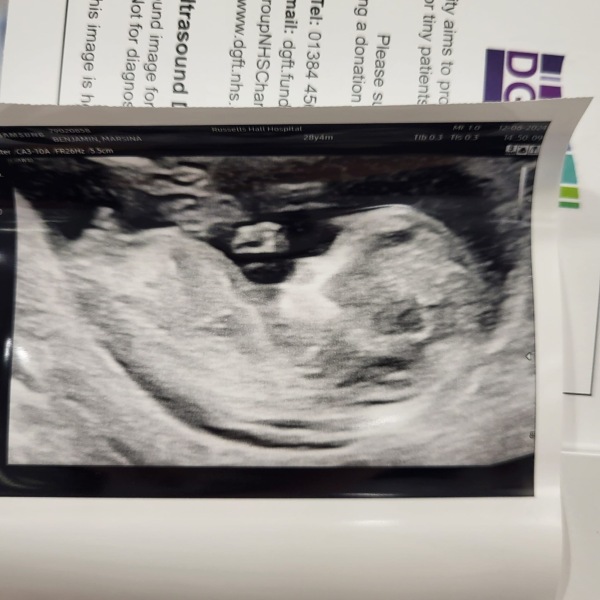

Marsonina · 18/06/2024 02:43

Hi all. This is 12 weeks scan. Can anyone with experience know the gender from these pictures ? I hope there won’t be guesses and some experience answers. Thanks.